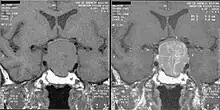

Magnetic resonance image of a pituitary macroadenoma that caused acromegaly with compression of the optic chiasm

An MRI of the brain focusing on the sella turcica after gadolinium administration allows for clear delineation of the pituitary and the hypothalamus and the location of the tumor. A number of other overgrowth syndromes can result in similar problems.